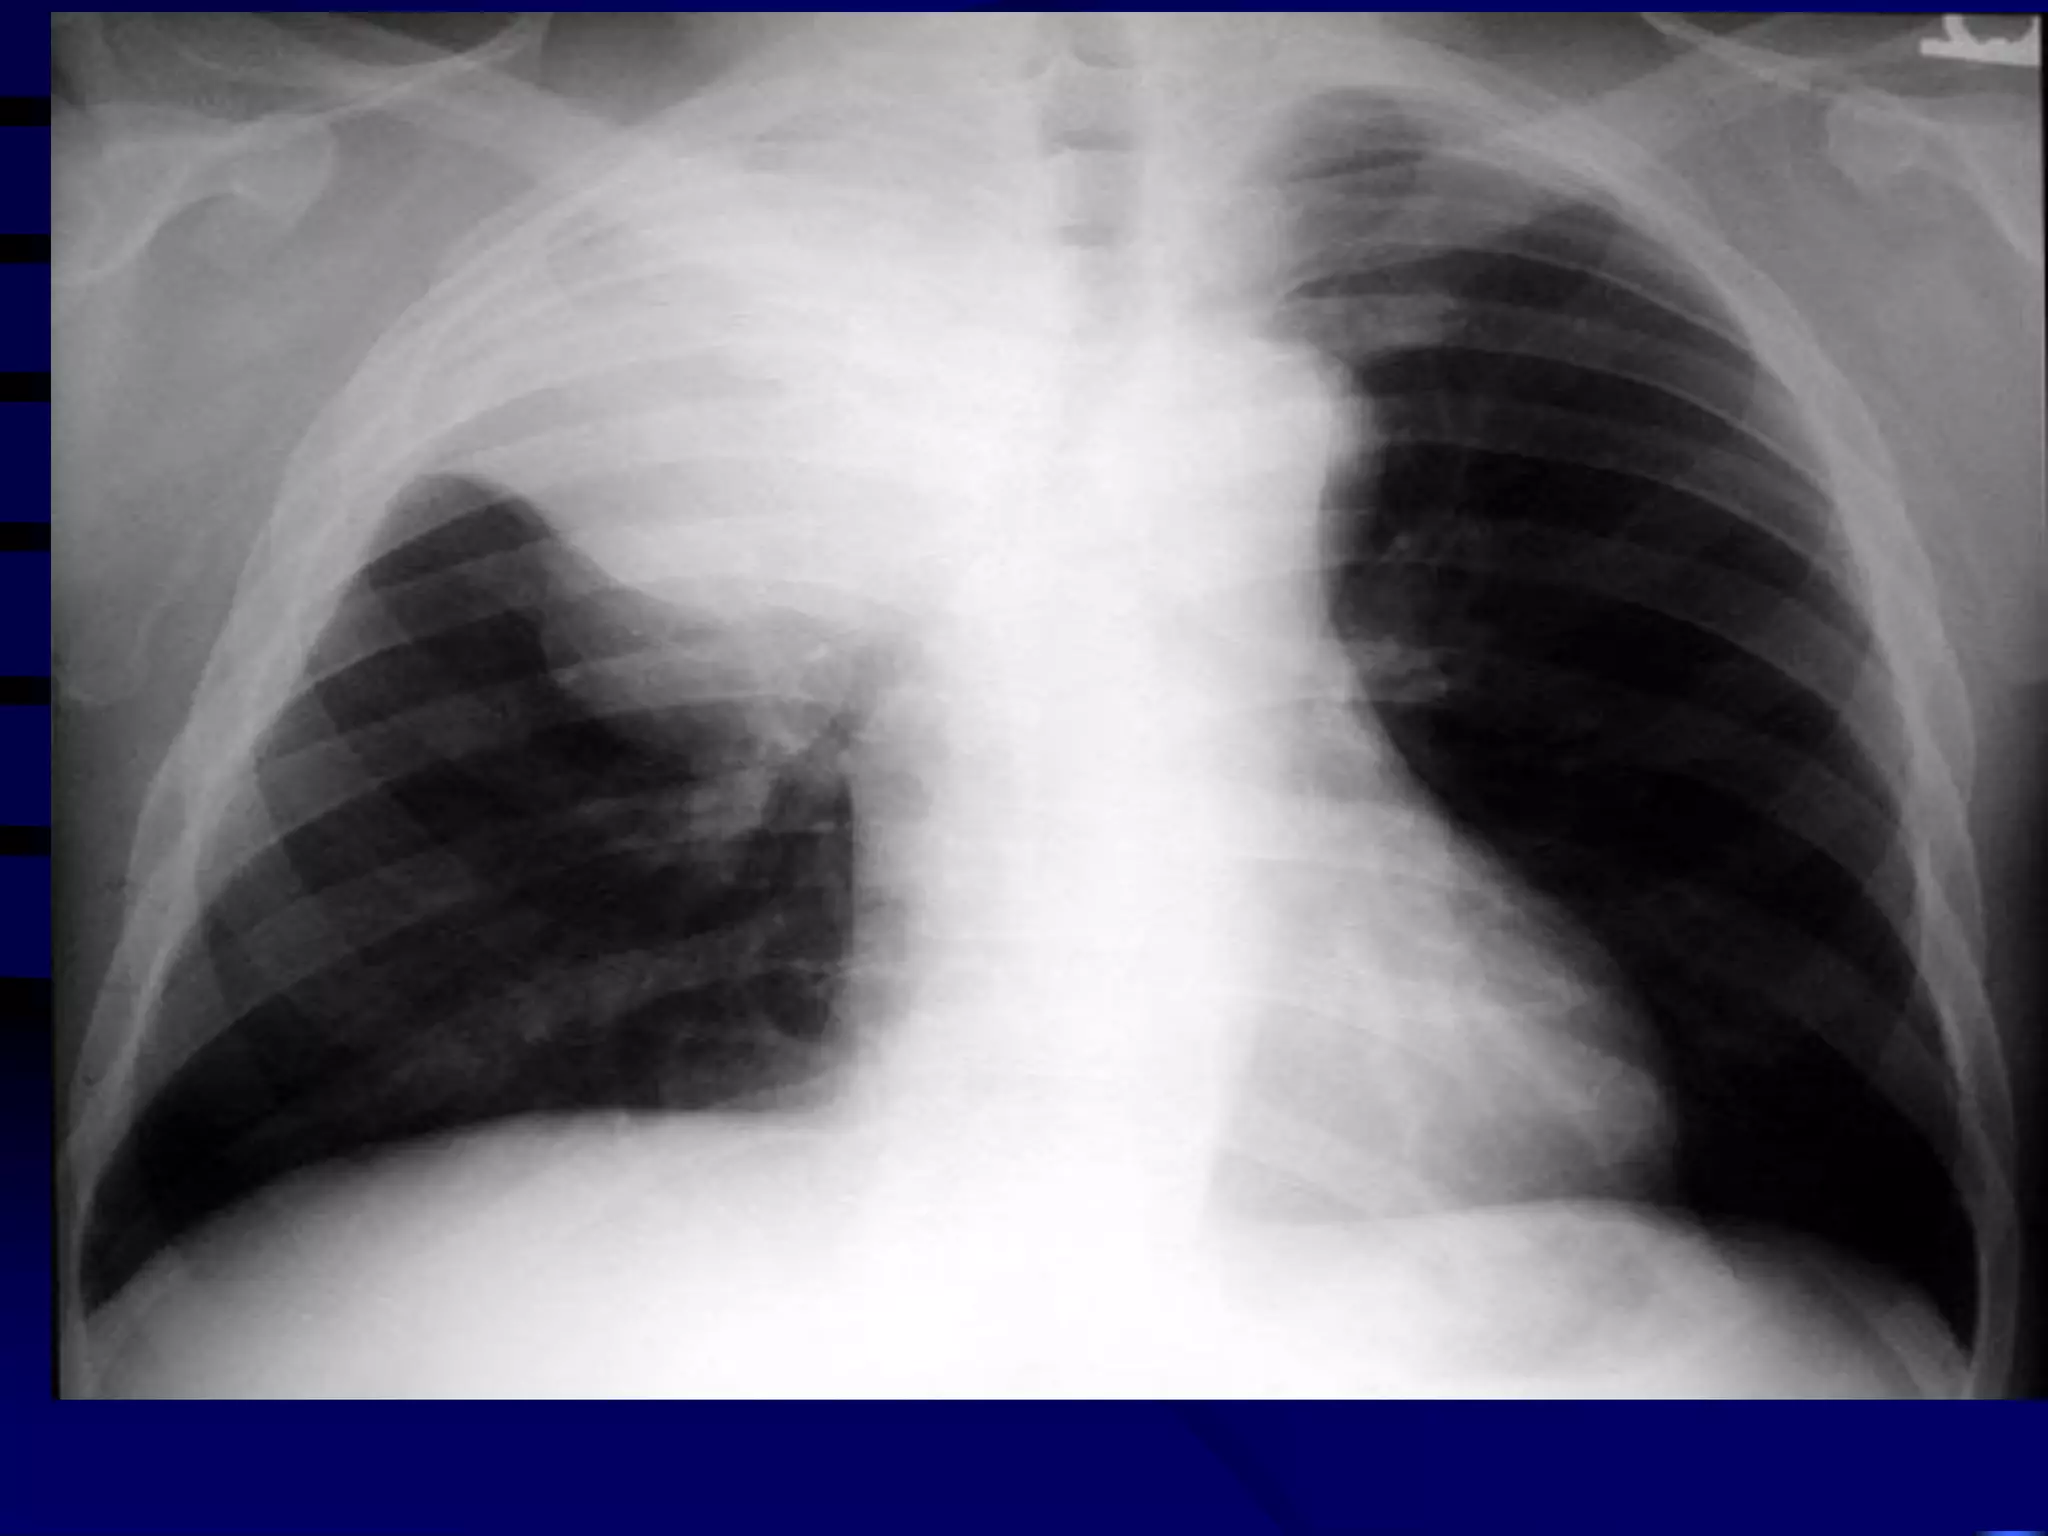

CXR Findings

Primary TB:



Reactivated TB:

Lower or middle lobe infiltrates

Apical infiltrates/cavitation

Latent TB:

Usually normal

 Nodules in hilar area or upper lobes

 Pleural scarring/thickening

CXR Findings  Primary TB:   ReactivatedTB:   Lower or middle lobe infiltrates Apical infiltrates/cavitation Latent TB: Usually normal  Nodules in hilar area or upper lobes  Pleural scarring/thickening 